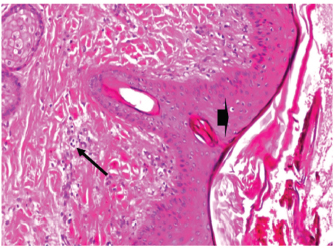

At 7 days post wounding; the inflammatory reaction was moderate and characterized by polymorphonuclear cells and macrophages infiltration with the presence of small scab covering the wound surface. Early evidence of epithelization was detected and represented by the proliferation of epidermal epithelium under the scab. There was marked thickening and hyperplastic proliferation of epidermal epithelium at the free wound edge (Fig. 6). The dermal tissue underlying the wound area showed few polymorphonuclear cells infiltration and more abundant mononuclear cells. Fibroplasia and angiogenesis were detected in the dermis and more extensive in deeper areas of the dermis which characterized by fibroblast and angioblast proliferation forming immature young granulation tissue (Fig. 7). At 14 days post wounding, the wound area was covered by a complete layer of epidermal epithelium indicating a good epithelization rate of the wound. Proliferation of cutaneous appendages was detected. The newly formed epithelium was thick and showed partial keratinization and epithelial differentiated stratum containing polyhedral keratinocyte with the appearance of keratohyalin granules in their cytoplasm (Fig. 8). The dermal tissue showed deposition of parallel well organized and interconnected collagen bundles that arranged parallel to epidermis associated with enhanced angiogenesis represented by well-developed blood capillaries (Fig. 9). At 21 days post wounding, remodeling of the formed epithelium with relatively small scar formation and mild restoration of skin appendages. Keratinized and differentiated stratum comprising the covering epithelium and the newly formed skin appendages from the basal epidermal epithelium were detected (Fig. 10). The dermal tissue revealed well-formed organized tissue consisted of parallel compact and interconnected bundles of collagen with scant angiogenesis (Fig. 11). At 28 days post wounding, well-formed scar tissue covering highly cellular organized tissue was detected (Fig. 12). The dermal tissue revealed well-arranged compact collagen bundles containing scarce blood vessels (Fig. 13).

Fig. 6. Skin of a goat from electroacupuncture group at 7 days post wounding showing early evidence of epithelization, hyperplastic proliferation of epidermal epithelium (arrow head) at the free wound edge, and moderate inflammatory cells infiltrations in the dermis (arrow), (HE ×100).

Fig. 7. Skin of a goat from electroacupuncture group at 7 days post wounding showing fibrin exudation at wound surface with dermal edema, hemorrhages (arrow) with moderate mononuclear cells infiltration associated with formation of immature granulation tissue consisted of fibroblast and angioblast forming small blood channels (arrow head), (HE ×200).